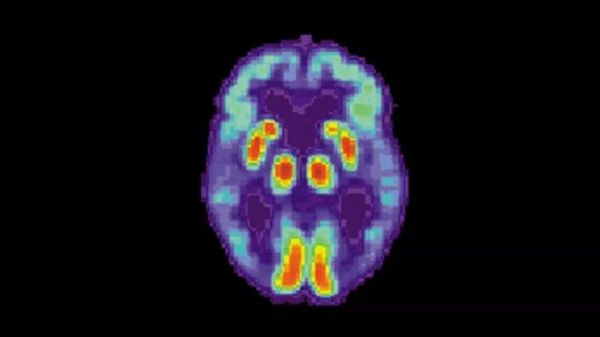

常见的发诊断方法是一种常用工具叫做正电子发射断层扫描(PET),主要原理是通过扫描测量大脑中特定分子(如葡萄糖)的水平来判断症状严重程度的。葡萄糖是脑细胞的主要燃料来源,细胞越活跃,消耗的葡萄糖就越多。随着脑细胞的病变和死亡,葡萄糖消耗逐渐减少,最终没有葡萄糖。

其他一些类型的PET扫描,旨在寻找与阿尔茨海默病有关的蛋白质,但葡萄糖PET扫描更常见且更便宜,尤其是在较小的医疗机构和发展中国家,因为它们还被用于癌症分期。/因此,放射科医生多使用这些扫描试图通过寻找大脑中(额叶和顶叶中)降低的葡萄糖水平来检测阿尔茨海默氏症。但问题是,由于该疾病是一种缓慢的进行性疾病,因此葡萄糖的变化非常微妙,难以用肉眼观察。

阿尔茨海默氏病患者脑部的PET扫描(图片来源:National Institute on Aging)

随着人工智能技术的发展,科学家们有了将机器学习与PET扫描相结合以更早、更可靠地诊断早期阿尔茨海默病的想法。